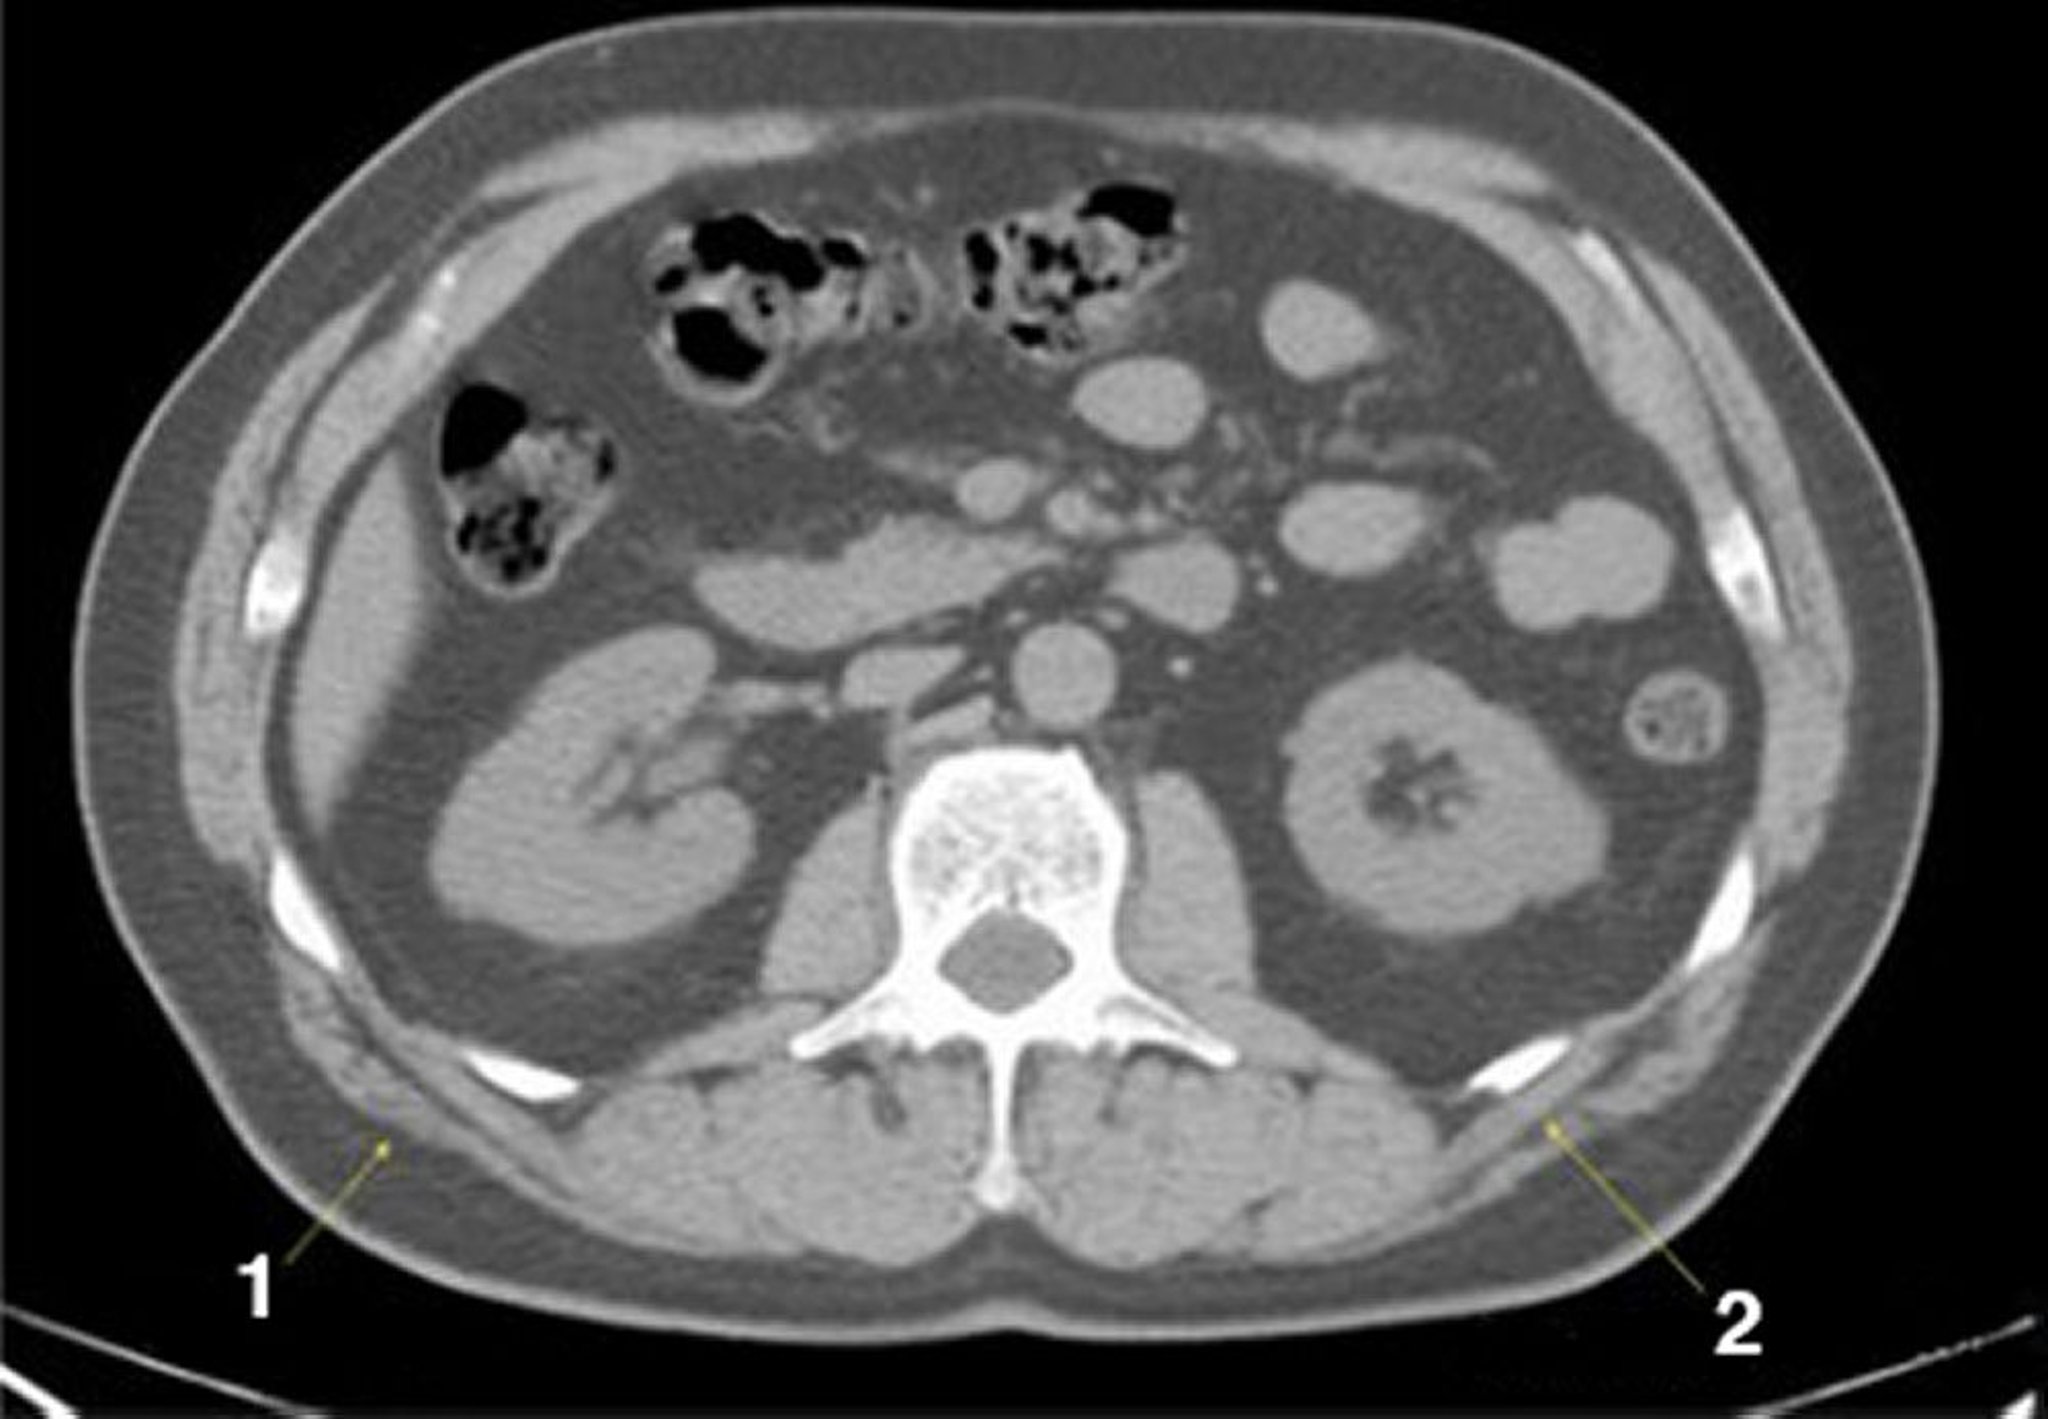

TC senza contrasto dell'addome e della pelvi che mostra un'anatomia normale (Slide 15)

1 = latissimus dorsi; 2 = serratus posterior.